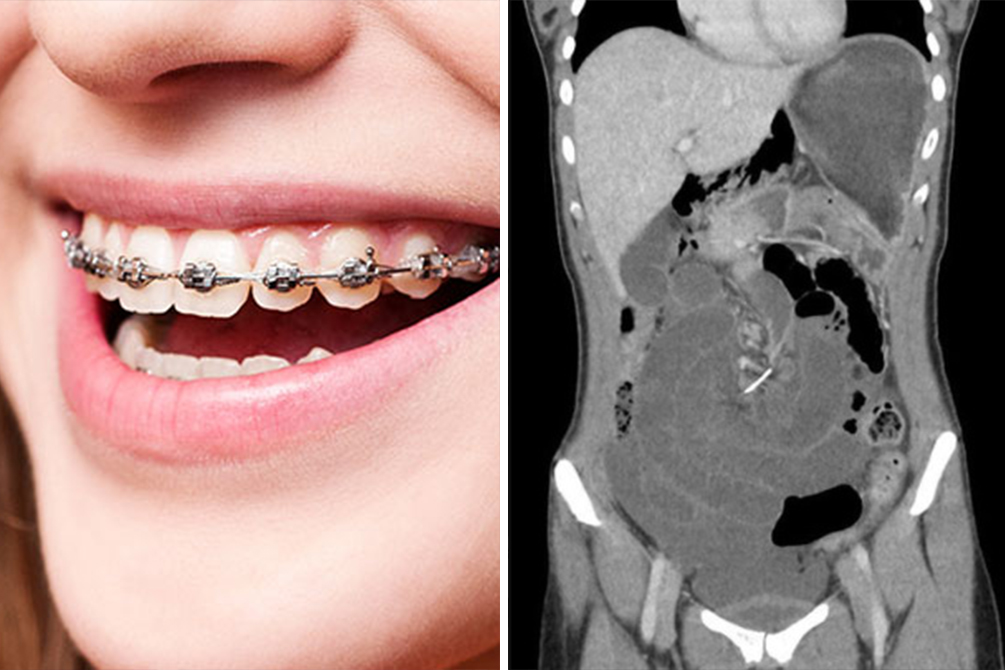

A australiana de 30 anos foi ao hospital se queixando de dores e câimbras na região abdominal e precisou passar por uma cirurgia de emergência